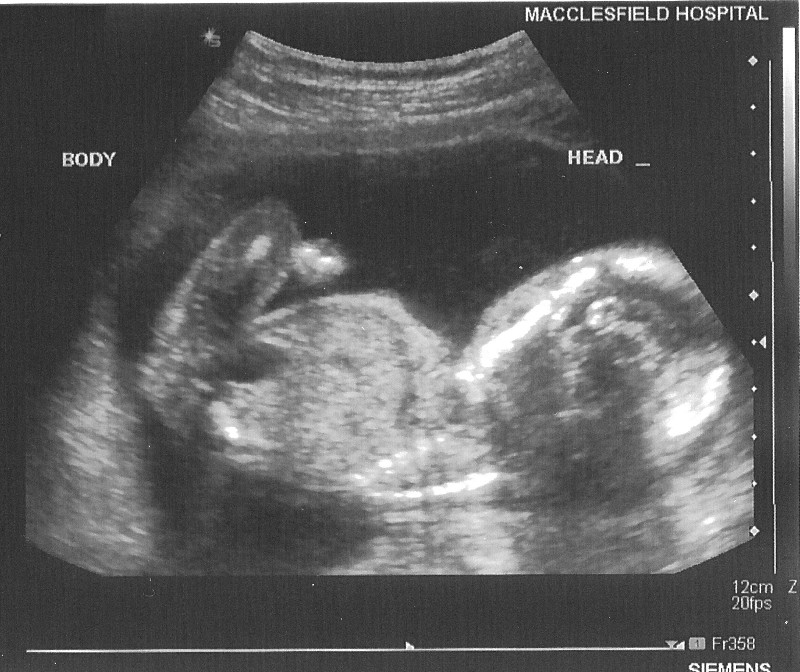

20 Week Hospital Scan on 14 March 2006